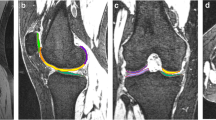

A senior-level radiologist, who was blinded to the volunteers’ clinical information, evaluated the extent of cartilage degeneration and hydrarthrosis. Cartilage score criteria was obtained using the Whole-Organ Magnetic Resonance Imaging Score (WORMS) and ranged from 0 to 2. Knee cartilage was automatically segmented into 21 subregions [14] using post-processing prototype software (MR Chondral Health, version 2.1, Siemens Healthcare, Erlangen, Germany). This software automatically divides the knee cartilage into three main parts—femoral, patellar, and tibial cartilage—consisting of 21 cartilage subregions. The T2* maps were automatically registered to 3D DESS images by prototype software. The cartilage volume and mean T2* relaxation time for each subregion were also derived automatically by the software. The corrected slice was the slice that needs to be manually adjusted after automatic segmentation (Fig. 1). The T2* relaxation time of cartilage in the knee was measured by the same doctor twice a week apart to test consistency among observers. The automatic segmentations were manually corrected to increase overall segmentation accuracy. The Dice coefficient was used to quantify the amount of change performed on the automatic segmentation [5, 11]. The Dice correlation between automatic segmentation A (fA(x)) and manual correction based on the automatic segmentation B (fB(x)) was defined as in Equation: Dice (fA(x),fB(x)) = 2·fA(x)·fB(x)/(fA(x) + fB(x)). Levels of hydrarthrosis and cartilage scores (by WORMS) were determined to analyze their influence on the segmentation accuracy of each cartilage subregion.

With the increase in joint effusion, the Dice coefficient in the patella increased somewhat, but the difference was not statistically significant. The femoral condyle and patella had lower Dice coefficient (0.9969 and 0.9922, respectively) than the other regions of the knee cartilage when the cartilage score was 0 in the control group. The femoral condyle and patella had the lowest Dice coefficient (0.9900 and 0.9889, respectively) when the cartilage score was 2 in the hydrarthrosis group (Fig. 2).

Cartilage score influence on Dice coefficient of the automatic cartilage segmentation software in the control and hydrarthrosis groups. Hydrarthrosis significantly decreased the Dice coefficient of moderate degenerated patellar cartilage and distal femoral cartilage but increased the Dice coefficient of mild degenerated proximal tibia cartilage. (WORMS 0 = normal; 1 = mild; 2 = moderate)

These results suggest that use of the automated segmentation software results in a Dice coefficient of each subregion of higher than 0.9. The location of subregions, extent of hydrarthrosis, and level of cartilage degeneration are the most important factors affecting the accuracy of automatic segmentation. Automatic segmentation software can mistake some of the fluid accumulation at the edges of subregions, resulting in an overestimate of cartilage volume. These areas deserve greater attention during manual correction to increase segmentation accuracy in these parts. In all 21 subregions, the subregions with the most corrected slices were located in the medial anterior, central trochlea and lateral trochlea of the femoral condyle, medial inferior, and medial central of the patellar, and the medial anterior of the tibia condyle. These subregions were likely influenced by hydrarthrosis. Under the influence of hydrarthrosis, the Dice coefficient for automatic segmentation of the femoral condyle and patellar cartilage decreased when the cartilage score was 2.

The evaluation of T2* has been shown to be capable of characterizing different degrees of cartilage degeneration [15]. It had been proposed as a robust biomarker of articular cartilage degeneration in several joints [16, 17]. The advantages compared to T2 mapping include shorter scan times and higher SNR [5]. In this study, the presence of hydrarthrosis and a higher cartilage degeneration score decreased T2*. According to the literature, T2* may be susceptible to the spatial macromolecule architecture and its influence on water molecule mobility [5, 18]. In this study, failure of the automatic segmentation software to distinguish the contour of the cartilage occurred mainly in articular cartilage near the fluid accumulation. A segmentation algorithm with increased robustness against synovial fluid is currently being integrated, but was not available for testing at the time of this study. The boundary between articular effusion and articular cartilage was not clearly visible. The T2* relaxation times of cartilage subregions extracted with manually corrected segmentation was decreased compared to those extracted with automatic segmentation. Articular effusion was recognized as articular cartilage by the automatic segmentation, resulting in the increase of the T2* relaxation times in the uncorrected subregions.